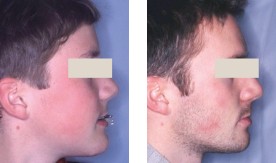

Parodontie et orthodontie : le traitement idéal des maladies parodontales

Cet article présente le concept de Régénération Prothétique Guidée (RPG) sur piliers dentaires (fig. 1). Le diagnosticDans la zone antérieure maxillaire,...La communication, fonction prioritaire de l’assistante en parodontie